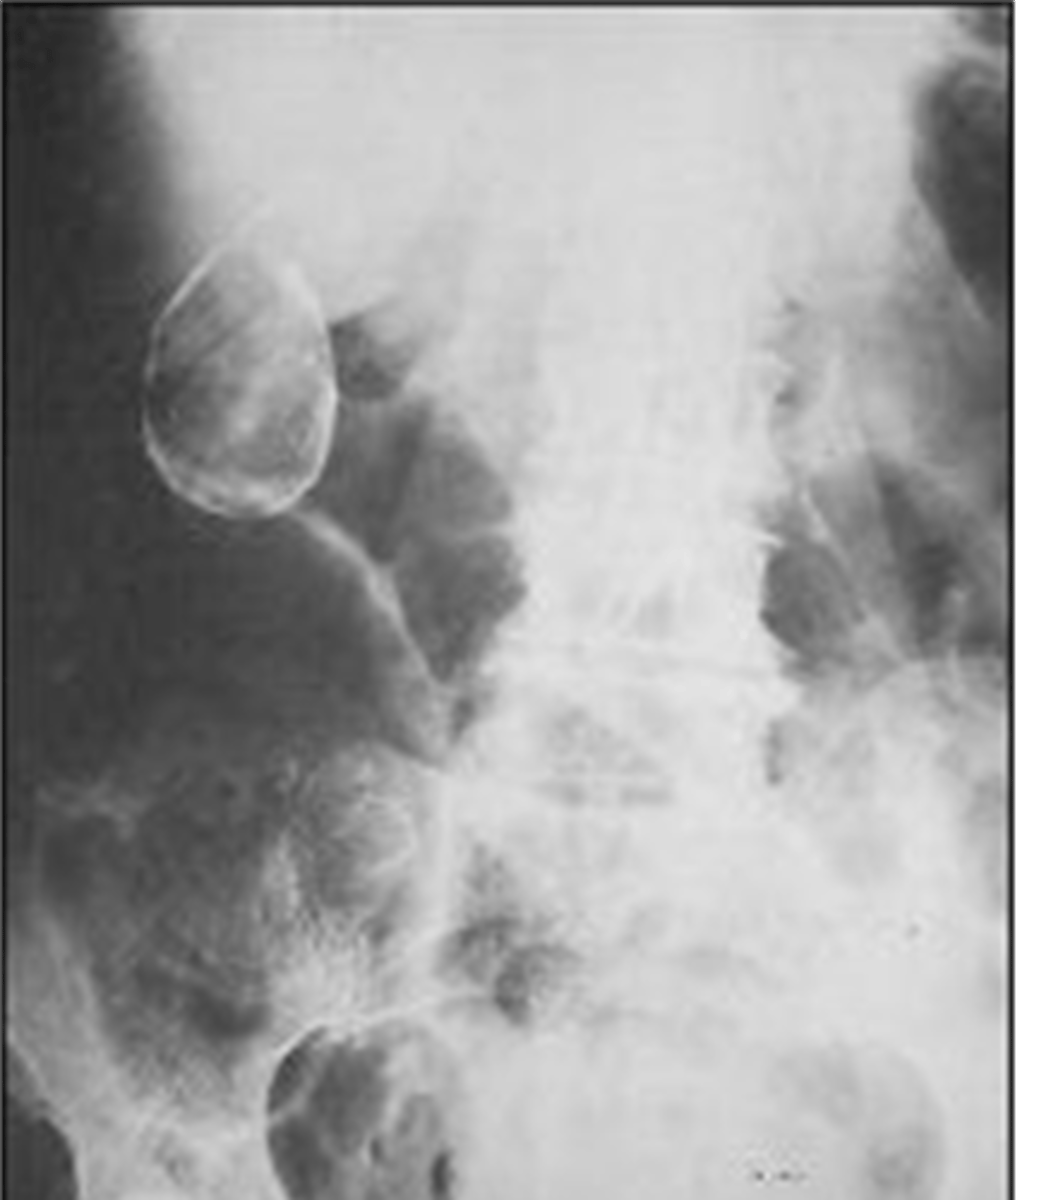

Lamellar "laminated" pattern

amorphous "popcorn" calculi

porcelain gallbladder